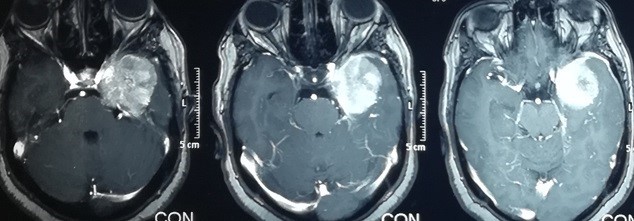

ورم سحائي بقاع الجمجمةبالفص الصدغي الايسر

left temporal lobe meningioma

Brain magnetic resonance imaging, cross-sections of a 56-year-old woman suffering from visual impairment and severe headaches. As shown in the pictures in the upper row, the tumor is located in the left temporal lobe, pressing on the carotid artery and the optic nerve on the left side. And the bottom row is the x-ray view of the same patient four months after successful surgery to remove the tumor without any complications.